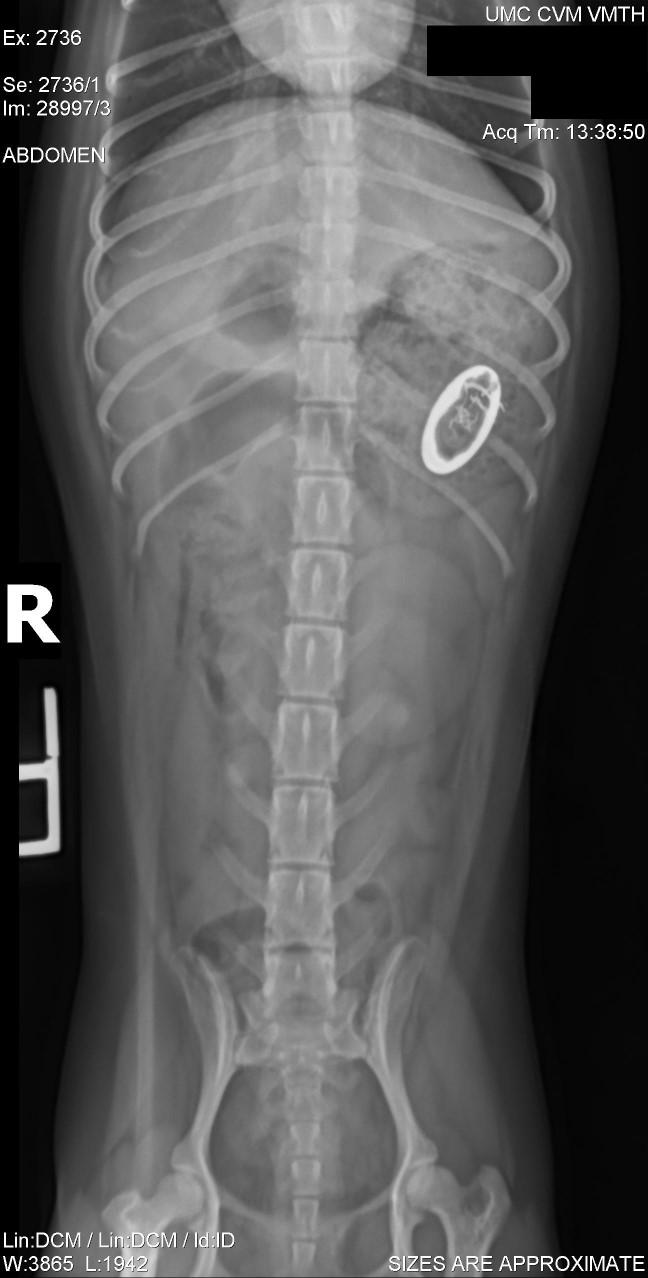

•Adultonsetpododemodicosiswithsecondarybacterialpyoderma

WhatNow?

•Re-evaluatehistory

•Appropriatetestingformostlikelyprimarycauseof adultonsetdemodicosis

•Serumbiochemistry

•ACTHstimulation

•T4/TSH

•FNAlymphnodes

•Imaging

Treatment

•IatrogenicAdultOnsetpododemodicosiswithsecondarybacterial pyoderma

•3prongedapproachformites:

•#1:Killthebacteria

•#2:Killthemites

•#3:Topicalfollicleflusher

•Alternativetherapyforpruritus

Isthisasuperficialordeepinfection?Howdothetreatmentsofthesediffer?